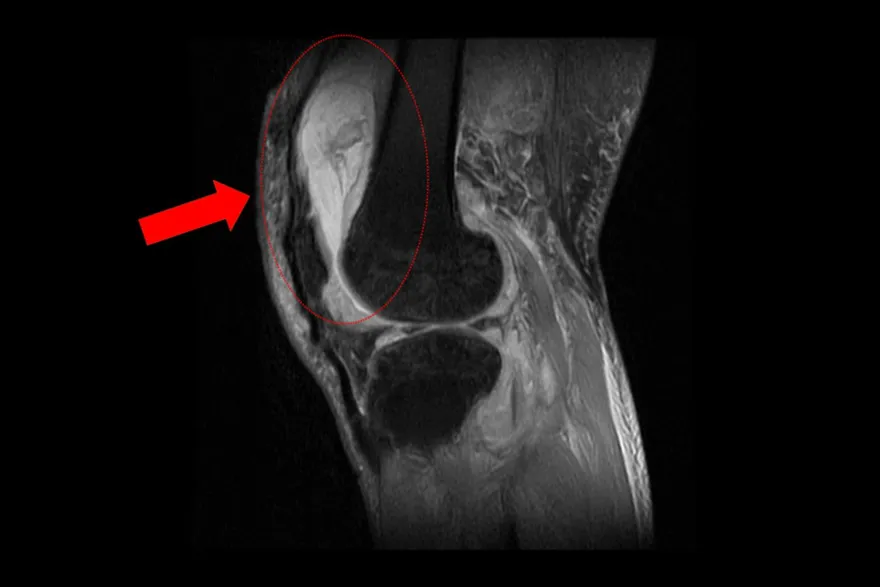

骨性膝關節炎

退化性關節炎

膝關節健康促進方案

內側摩擦症候群

保膝手術

關節鏡軟骨再生促進手術

護膝運動

人工膝關節

高位脛骨矯正手術

膝蓋保養

關節保健

膝關節

骨結核

肺外結核

慢性膝蓋疼痛

關節鏡清創手術

抗結核藥物治療